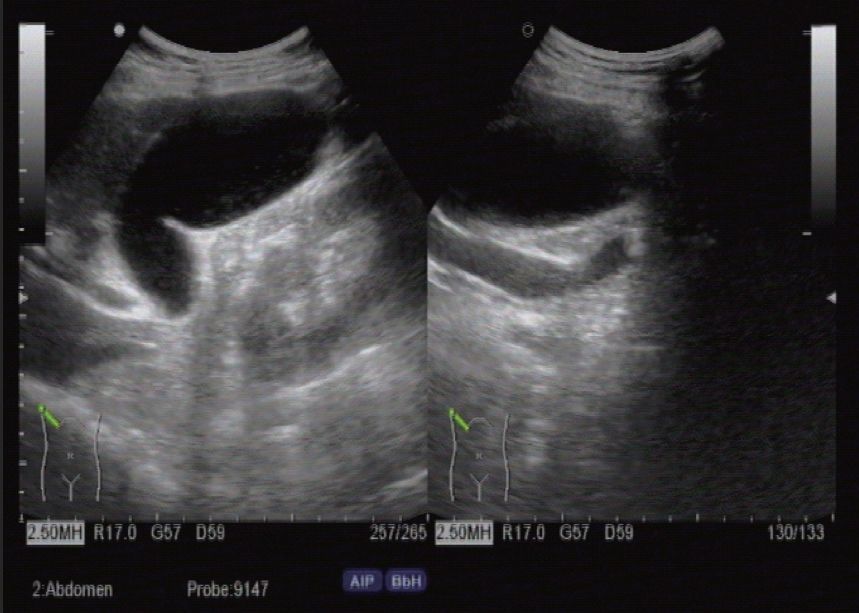

(2) 病例

1) 病史:患者女,43岁,突发右上腹疼痛、恶心、呕吐,体温38.6℃。查体Murphy征阳性。

2) 超声描述:胆囊体积增大,壁毛糙增厚,胆汁透声可,腔内未见明显异常回声。胆总管上段扩张,腔内可见一强回声光团伴声影,位置不随体位变化而改变(图8-3)。

3) 超声诊断:急性胆囊炎、胆总管上段结石嵌顿。